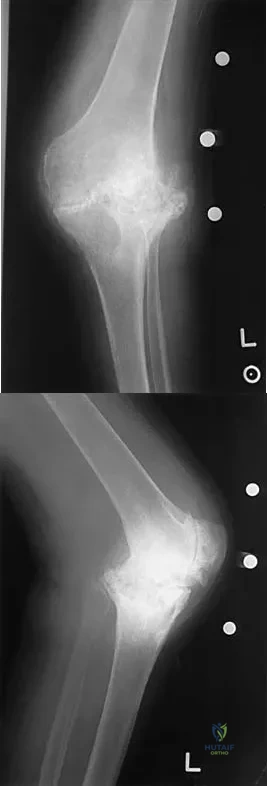

Question 99

Figures 5a and 5b show the radiographs of an active 52-year-old man who has increasing knee pain and progressive varus deformity after undergoing total knee arthroplasty 7 years ago. Examination reveals a small effusion, but he has good motion and stability. What is the most likely diagnosis?